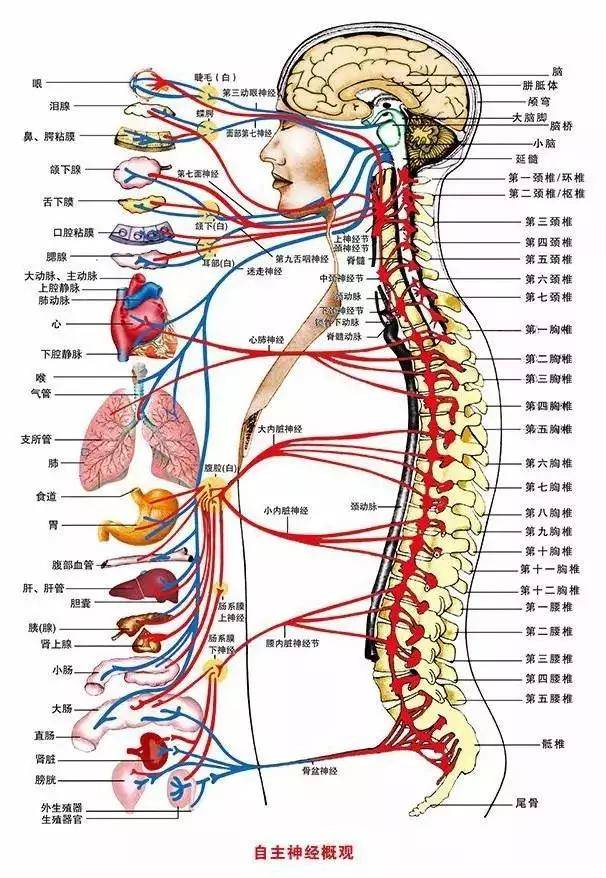

ˋ▽ˊ 心脏神经官能症的危险征兆:如何巧妙避免这4大饮食陷阱!心脏神经官能症是一种与心脏相关的常见问题,主要由于心脏神经系统的功能受损。这种功能受损会干扰自主神经系统的正常工作,导致心脏功能出现各种异常。在临床中,患者可能会经常体验到心慌、胸闷、气短以及身体乏力等不适症状。 然而,许多人对心脏神经官能症的危害性认识不...